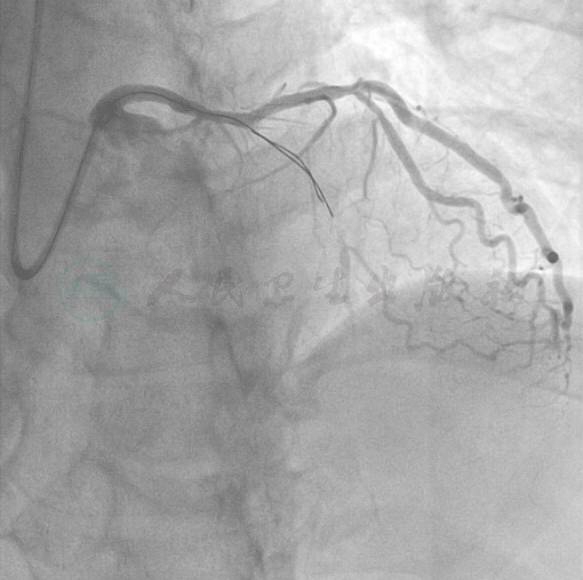

冠状动脉造影结果

选用右侧桡动脉径路,6F血管鞘。造影发现(图1~图3):左主干未见明显狭窄或阻塞性改变,前降支起始部100%闭塞,远端可见来自回旋支侧支循环。回旋支近中段弥漫性病变,狭窄最重90%。右冠状动脉:近段100%闭塞。

图1 右冠造影

图2 左冠造影1

图3 左冠造影2